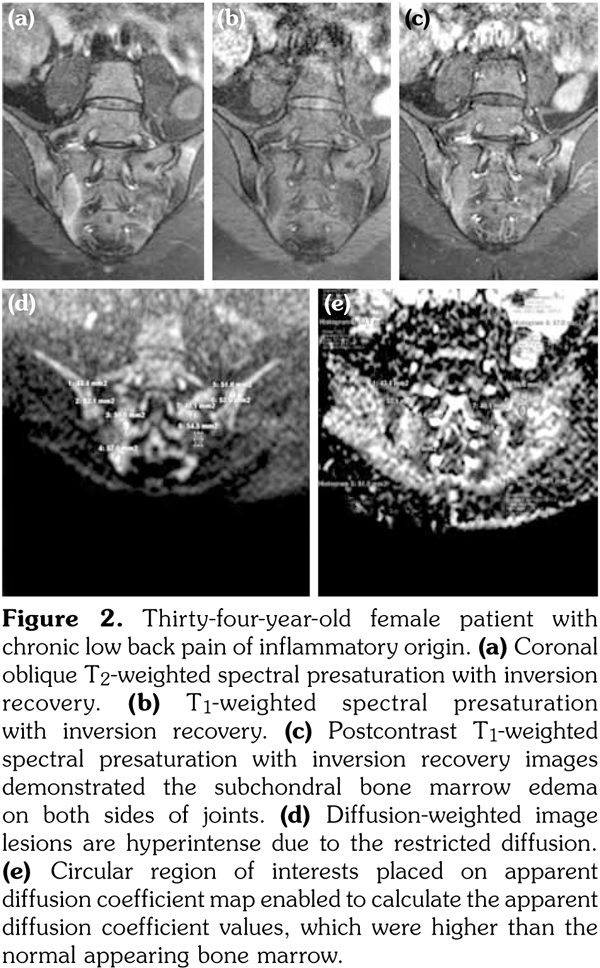

Sacroiliac joints were assessed according to ankylosing spondylitis criteria. Before evaluation of standard MRI protocol, patients’ information was removed from images. Afterwards, two experienced radiologists evaluated the images for the presence of inflammatory activity twice at separate sessions to assess interobserver variability. Following the examination of T2-weighted SPIR, contrast- enhanced T1-weighted SPIR, and DWIs at b values of 600 s/mm2, two radiologists and rheumatologists reached a consensus on the disease activity in the light of positive features of Berlin criteria. The DWIs were transferred to a separate workstation (Phillips, Extended MR workspace, 2.6.3.2.HF3, Netherlands). ADC maps were generated. T2-weighted SPIR images, contrast-enhanced images and diffusion-weighted images with ADC maps were put on the screen side by side. In the disease group, the hyperintense lesions on T2-weighted SPIR images and enhanced focuses on contrast- enhanced images were noted and the same lesions were marked on DWI images and ADC map. A circular ROI with a range of 40-75 mm2 was placed in those areas. In the control group a circular ROI was placed in the subarticular area of joints. Also, the same process was performed for the normal-appearing bone marrow areas near the joints of the disease group (Figure 2). Four standard measurements were conducted from each joint, including two on sacral and the other two on the iliac side for all patients (Figure 3). Additionally, two measurements were conducted from the fifth lumbar vertebra and one from each iliac wing (Figure 4). All measurements were performed twice. ADC values were expressed as square millimeters per second. The r-ADC ratio was calculated by dividing ADC value of subchondral bone or inflammatory lesions to ADC values of the fifth lumbar vertebra and iliac wings.

Disease and control groups were homogenous. There was no difference in the age and the sex distribution statistically (Table 1). Thirty-nine patients with chronic back pain were diagnosed as axial spondyloarthritis with sacroiliitis and had active inflammatory changes on MRI of sacroiliac joints. Seventeen patients were diagnosed as having chronic back pain of mechanical origin. Among 39 patients with active sacroiliitis, 23 had erosions on either sacral or iliac surfaces; eight patients had sclerosis either on the right sacral bone (RSB), left sacral bone (LSB), right subchondral iliac bone (RIB) or left subchondral iliac bone (LIB) detected by plain radiographs; and sixteen patients had periarticular fat deposits in the bone marrow. Three of all patients had ankylosis while 15 with active sacroiliitis had no structural changes on MRI.

In the inflammatory back pain group, mean ADC measurements of all sacral and iliac bones were significantly higher than that of patients with mechanic back pain (Table 1). There was no significant difference between the mean ADC values of the bone marrow of L5 vertebra and iliac wings in patients with active sacroiliitis and mechanic back pain (Table 1). The mean ADC measurements of active lesions for both sides of joints for iliac and the sacral bones were significantly higher than either normal- appearing bone marrow areas in patients with active sacroiliitis or in patients with mechanical back pain (Table 1).

When the r-ADC ratios of both groups’ normal- appearing bone marrow and inflammatory lesions calculated by fifth lumbal vertebra were compared, r-ADC values of active lesions were considerably higher than normal-appearing bone marrow areas both in patients with active sacroiliitis or in patients with mechanical back pain. There was no significant difference between the r-ADC values of both groups’ normal-appearing subchondral bones calculated with L5 vertebra chosen as the reference organ (Table 1).